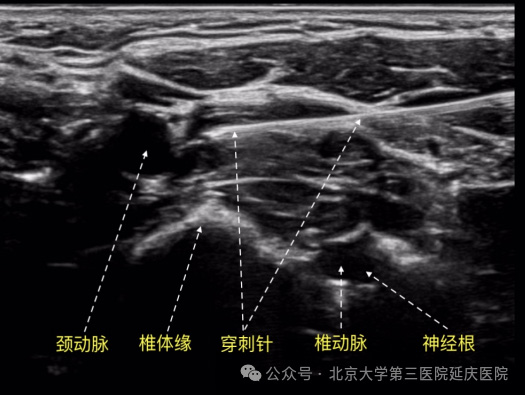

老百姓口中的“鼻炎针”是一种微创的神经调节疗法,指的是在颈部的星状神经节进行精准阻滞。

1.扩张血管,改善循环: 通过注射极低浓度的局部麻醉药,暂时阻断星状神经节的过度兴奋,可以扩张头面部的血管,改善鼻黏膜的血液供应,促进炎症物质代谢,从而缓解鼻塞。